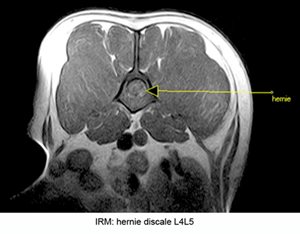

L'imagerie par résonance magnétique nucléaire (IRM).

Si quelques centres vétérinaires sont équipés en appareils dits de "bas champs", le développement de l'IRM en médecine vétérinaire en France reste encore à ses balbutiements. Lla carence en appareils performants dits de "haut champs" est une limite importante quant à la qualité des examens permise par la plupart des appareils actuellement accessibles.

Sur le rachis, sauf pour le diagnostic des kyste arachnoïdiens, du syndrome de Harnold Chiari, ou de certaines lésions intra-médullaires, les machines de bas champs sont moins performantes que les scanners multicoupes (dits multibarettes) désormais facilement disponibles en médecine vétérinaire.

La durée de l'examen par IRM, la très faible répartition géographique des appareils, leur manque de puissance et le coût très supérieur de l'examen par rapport à un scanner, font de l'IRM un examen de deuxième intention en terme d'exploration du rachis en médecine vétérinaire.

Il est par ailleurs important de noter qu'en médecine humaine, où les machines de haut champs très performantes sont pourtant facilement accessible, c'est les scanner qui demeure l'examen de première intention sur la colonne vertébrale.